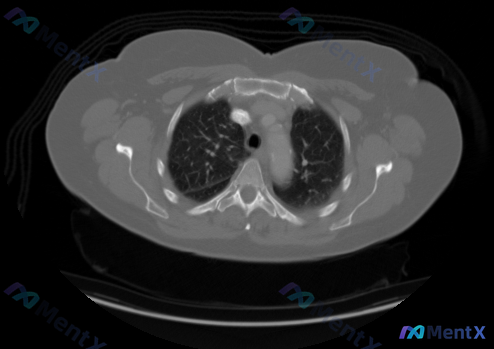

最近看到一个很有意思的影像分析场景,整理一下思路和大家讨论: 【背景与影像信息】 用户提供了一张胸部CT横断面图像(虽然说是纵隔窗,但对比度更偏向肺实质显示),直接问「图片中显示的癌症的类型和分期是什么」。 先看图像里的客观表现: - 纵隔淋巴结:气管前间隙、主动脉弓周围未见明显异常肿大淋巴结,大血...